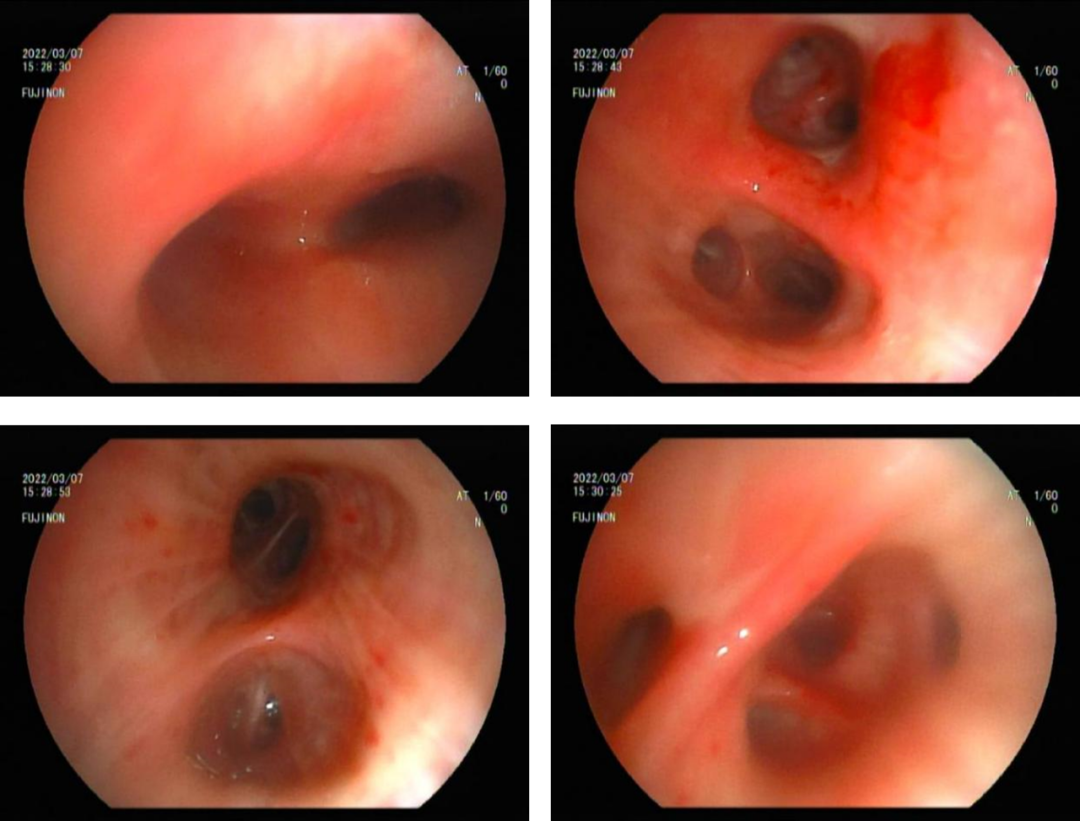

为明确患者肺部渗出原因,3月7日行电子支气管镜检查,气管镜见下可见气管及左、右主支气管腔内较多黄脓痰,吸尽后可见左右两侧各叶段支气管黏膜充血肿胀,左上叶、左下叶及右下叶基底段支气管管腔见轻度扩张样改变(图3),于右上叶前段行肺泡灌洗,灌洗液送检常规、细菌、真菌、抗酸杆菌及脱落细胞检测。

图3  气管下可见远端支气管扩张样改变